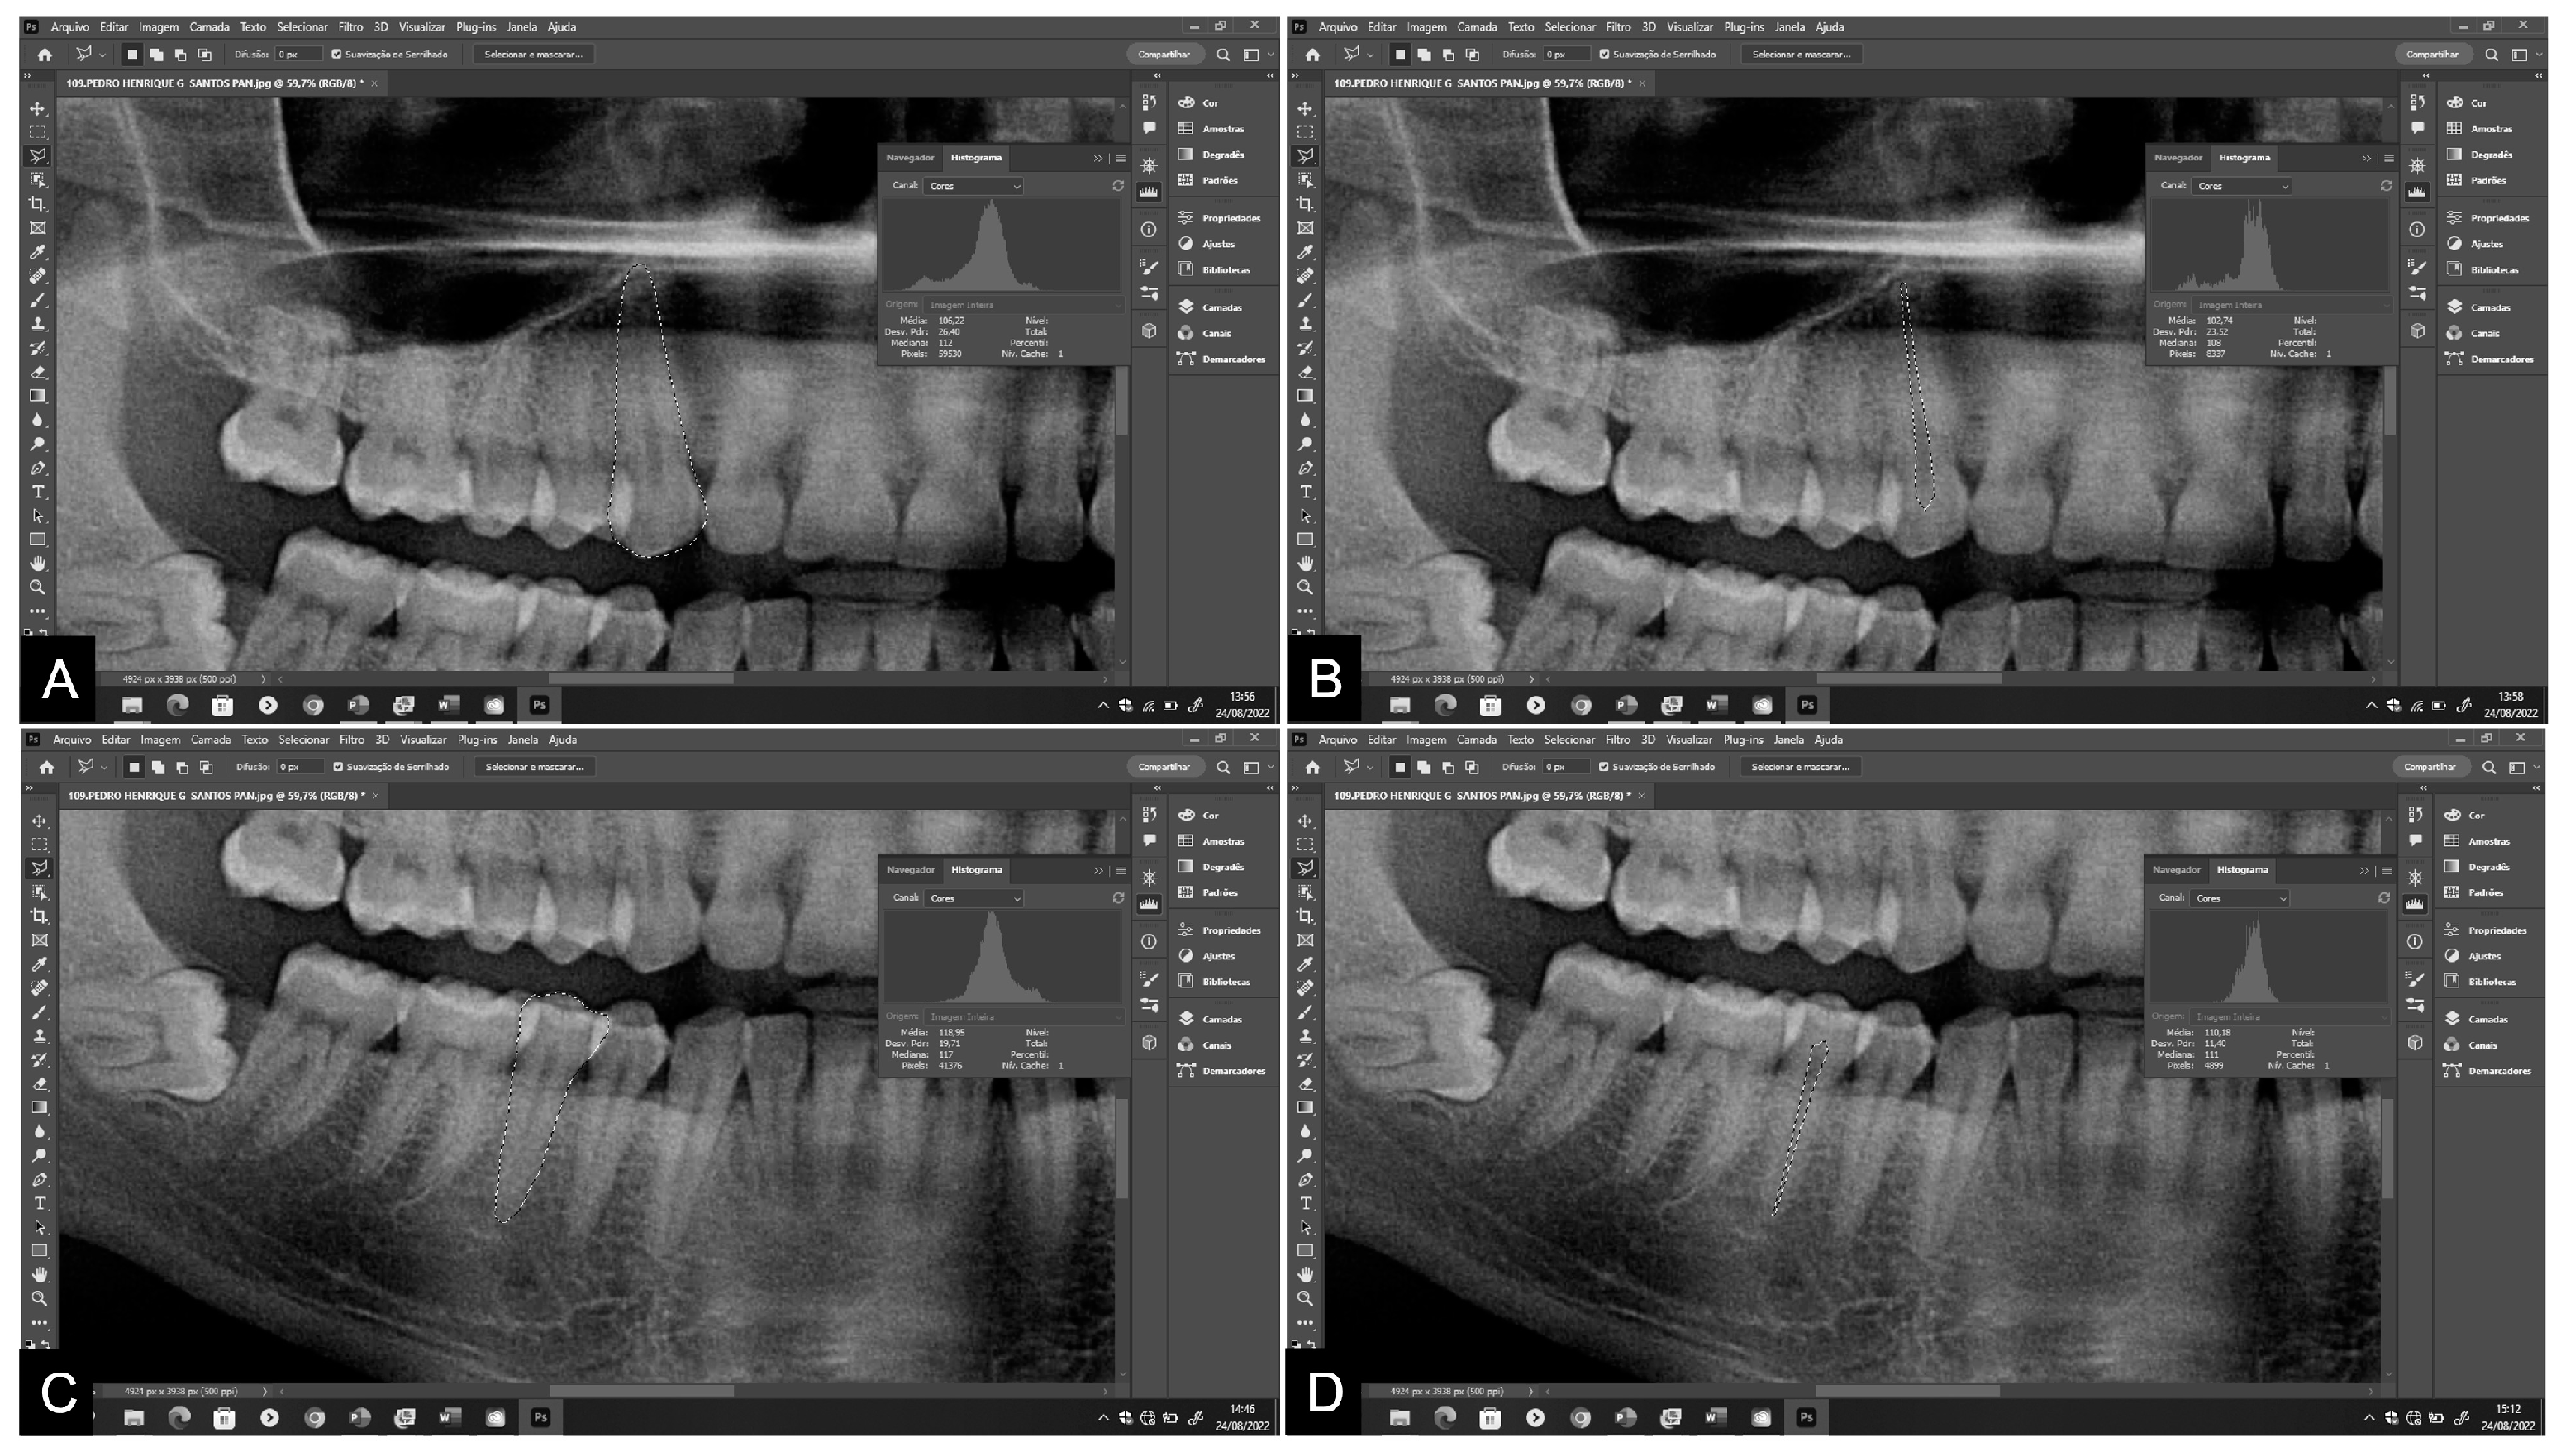

| Measure 1 | Measure 2 | p * | ICC (CI 95%) | |

|---|---|---|---|---|

| Pan T13/23 | ||||

| Tooth area | 19,013 | 18,762 | 0.579 | 0.999 |

| Pulp area | 2110 | 2081 | 0.606 | 0.997 |

| Peri T13/23 | ||||

| Tooth area | 22,501 | 22,686 | 0.643 | 0.990 |

| Pulp area | 2523 | 2552 | 0.239 | 0.996 |

| Pan T35/45 | ||||

| Tooth area | 15,139 | 15,610 | 0.717 | 0.999 |

| Pulp area | 1623 | 1619 | 0.116 | 0.998 |

| Peri T35/45 | ||||

| Tooth area | 15,656 | 15,540 | 0.055 | 0.999 |

| Pulp area | 1534 | 1449 | 0.557 | 0.995 |